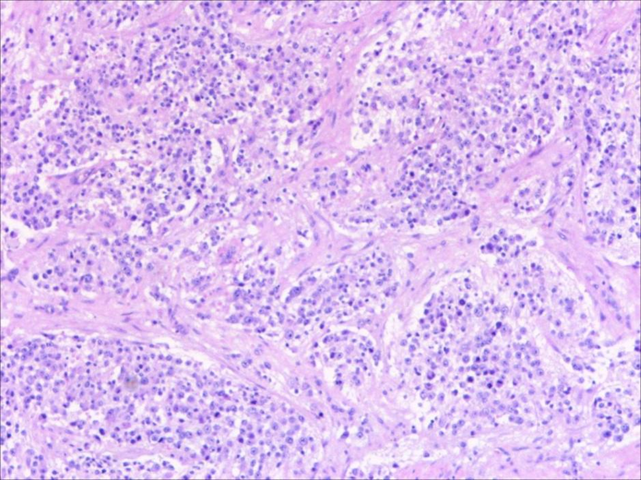

骨髓涂片:(右髂后)骨髓增生活跃,全片见大量转移肿瘤细胞团。

骨髓流式:(双侧髂后)可见NB表型的细胞,表达GD2、CD56、CDC81,不表达CD45。

骨髓活检病理(2021.08.18):(右髂后)符合NB骨髓转移。